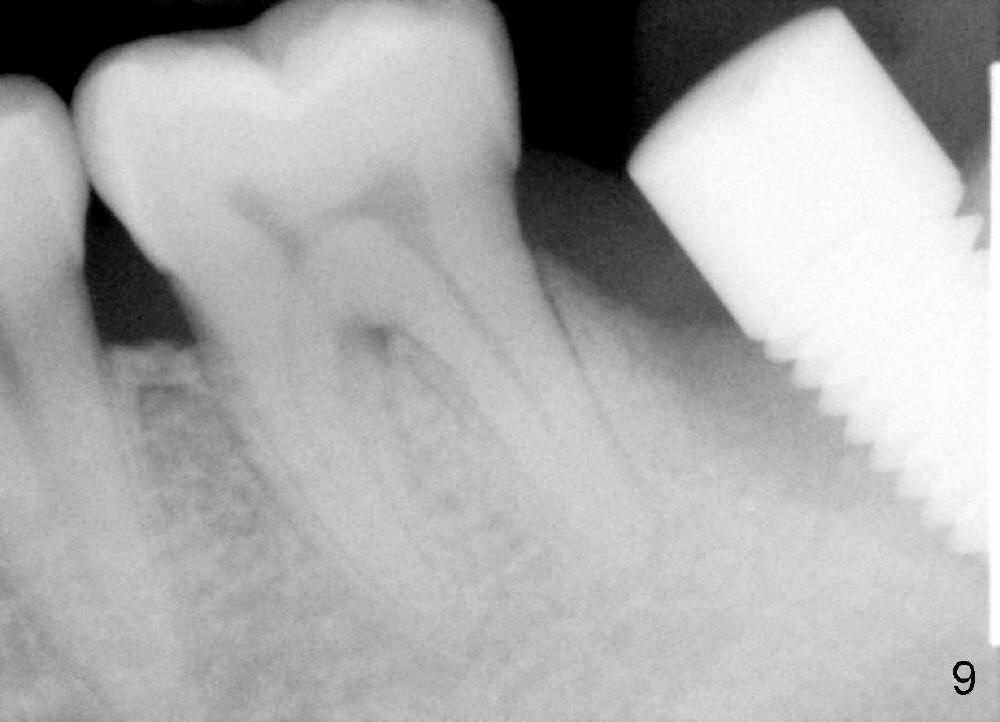

The lower left 2nd molar of a 45-year-old lady has perio-endo disease (Fig.1). The patient is not only very nervous, but also active in gag reflex. It is difficult to take good preop PA (Fig.1 *: ). Root canal therapy is performed. A relatively good PA is taken 1 year postop, again due to gap reflex (Fig.2). The tooth is still nonsalvageable (Fig.3). The last PA is taken 3.5 years before extraction and immediate implant. Infiltration anesthesia is administrated first. The patient experiences pain during early stage of osteotomy, but she does not report readily. Block anesthesia is added. Intraop PAs are taken with difficulty (Fig.4,5 with #1 sensor; 5 mm tap in place). Invasion of the inferior alveolar canal is not noted (Fig.5 dashed line). Oozing is a little more than expected. This is ignored. A 7x14 mm tapered implant is placed; the upper border of the inferior alveolar canal is not intact (Fig.6). Paresthesia area is defined next day (Fig.7). The implant is reversed for a few turns. Paresthesia area is reduced 19 days later (Fig.8). The implant is not stable. Follow up PAs are taken with difficulty (Fig.9-11). It appears that a shorter cylindrical implant is more appropriate for this case (Fig.11). The implant is stabilized with splinting with questionable result (Fig.12).